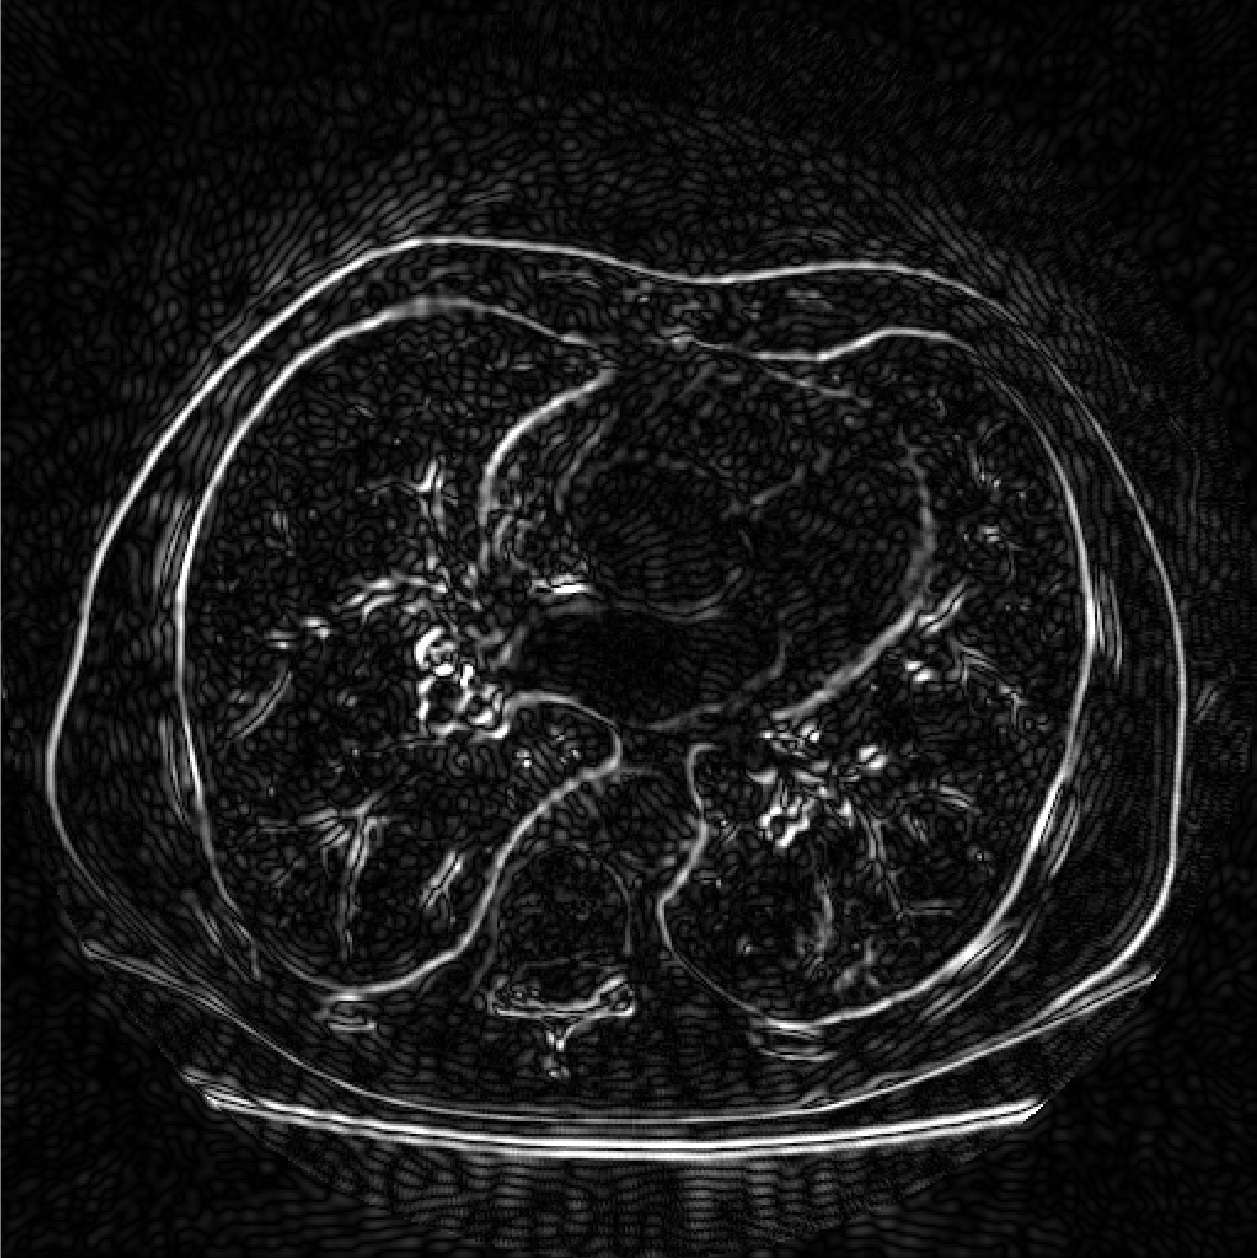

Fig.4 shows that our methods provide an improvement over the oblique method in our test cases. Fig.5 shows that our methods are more consistent when the resolution is relatively low. The reason is that oblique method truncates and estimates the sinc function, while we calculate the box spline exactly and have more accurate back projection. Fig.6 shows the absolute total error Etotalsubscript𝐸totalE_{\rm total} of the real CT image, the image reconstructed by oblique method suffers from higher error.

Refer to caption

(a)

(b)

(c)

Fig. 6: Absolute total error Etotalsubscript𝐸totalE_{\rm total} for the oblique method and box spline method on a real CT image. (b) and (c) are shown in the same scale to show the relative size of errors. (a) Ground truth. (b) Box spline, SNR = 16.7dB, SSIM = 0.84. (c) Oblique, SNR = 14.7dB, SSIM = 0.75.